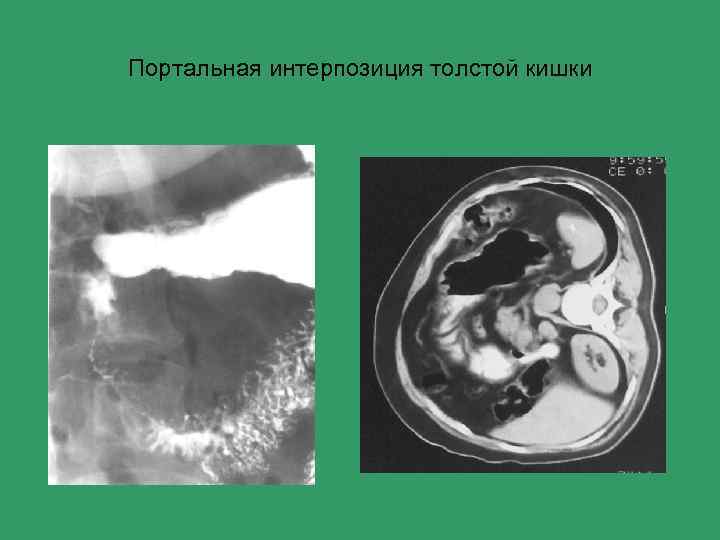

Механическая желтуха Основные причины 1) Жёлчнокаменная болезнь 2) Стенозы холедоха (рубцовые, опухолевые) 3) Опухоли головки поджелудочной железы 4) Анулярная поджелудочная железа 5) Портальная интерпозиция толстой кишки

Портальная интерпозиция толстой кишки